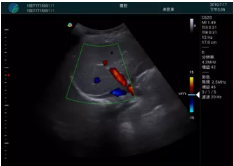

肝內(nèi)血管顯示清晰,血流敏感無外溢